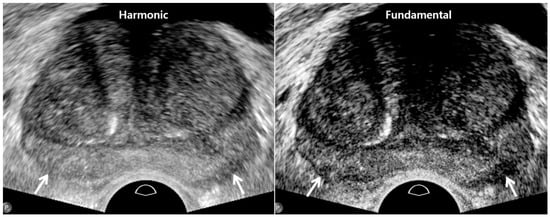

| TRUS Parameters | Old TRUS Techniques | New TRUS Techniques |

|---|---|---|

| US sequence | Harmonic imaging | Fundamental imaging |

| US artifacts | Rare | Frequent |

| Dynamic range | High | Low |

| Image resolution | High | Low |

| Tissue contrast | Low | High |